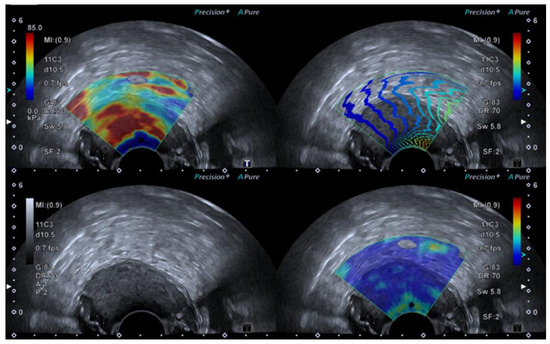

4.3. Elastography in Testicular Lesions